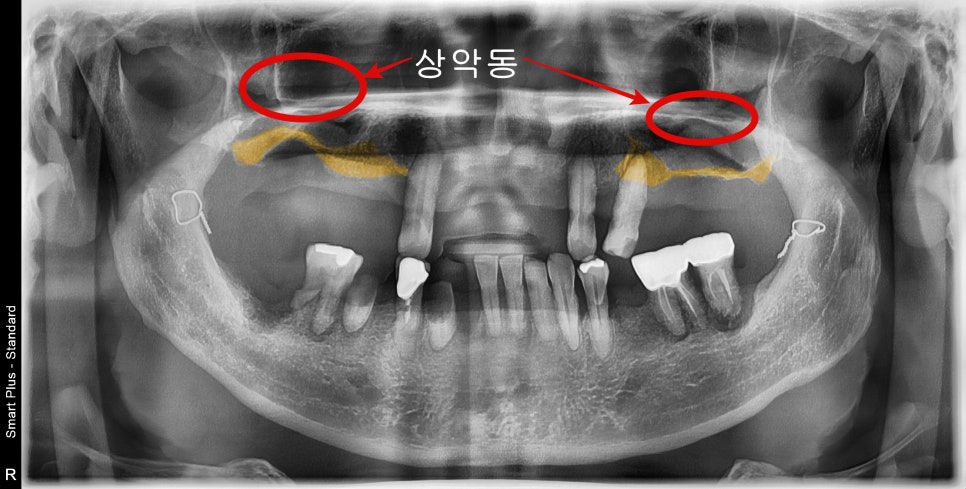

처음 내원해 주셨을 때 엑스레이 사진입니다.

과거에 턱 관련 수술도 받으신 흔적이 보이고

다수의 치아가 빠진 상태로 오랜 시간이 지나셨으며,

기존 치아들 주변도 치주염에 의해 동요도가 발생되었고 발치가 불가피해 보였습니다.

위턱뼈같은경우 치아가 상실된 기간이 길어 노란색으로 표시된 부위의 잔존뼈의 양이 너무 작았습니다.

수술을 위해서는 상악동 거상술이라고 하는 상악동 부위에 뼈를 만들는 수술이 필요해 보였습니다.